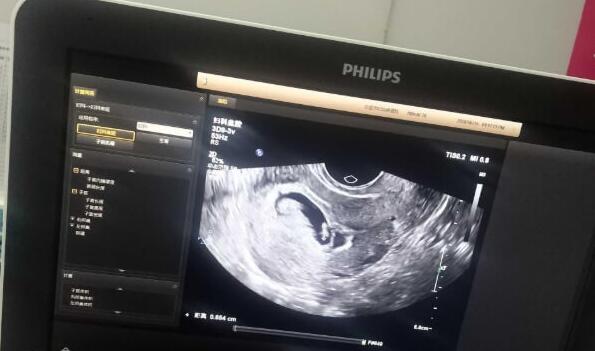

孕妇在妊娠期间需要定期进行产前检查,包括检查胎儿的心跳、胎位、胎盘位置等情况,及时发现问题并处理。